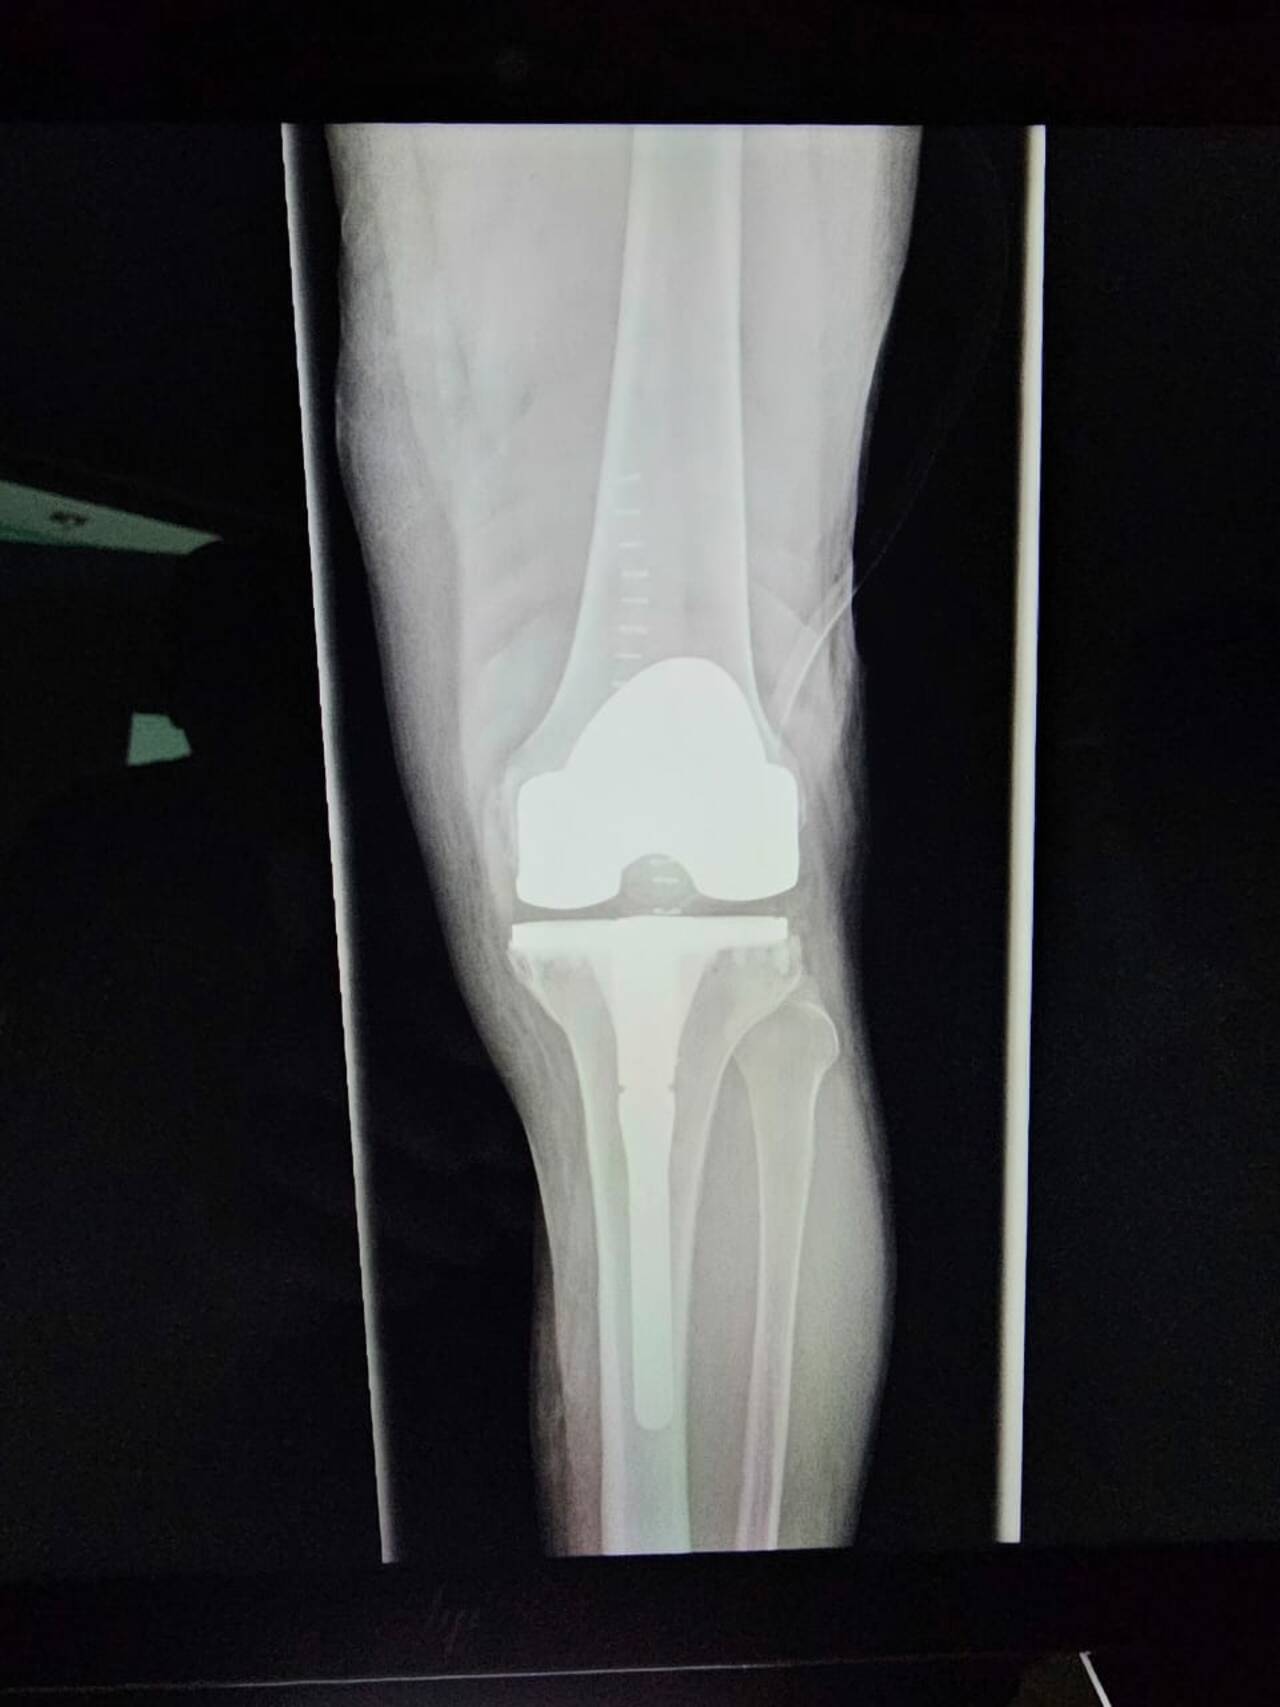

La satisfacción y el bienestar de nuestros pacientes son la mejor prueba del éxito de cada tratamiento. A través de testimonios reales y casos de éxito, compartimos historias de quienes han recuperado por completo la funcionalidad de sus rodillas y han vuelto a sus actividades diarias sin dolor ni limitaciones.

Cada paciente es un testimonio de compromiso, excelencia médica y el impacto positivo de los tratamientos personalizados en artroscopia y reconstrucción articular. ¡Descubre cómo un enfoque especializado puede transformar vidas!